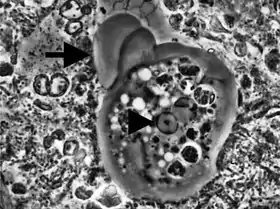

المُتَحَوِّلَةُ اللِّثَوِيَّة هي أميبا انتهازية،[2][3][4] وهي أول الأميبيات التي يتم وصفها في البشر. توجد في الفم،[5] داخل الأغشية الحيوية للجيبة اللثوية بالقرب من قاعدة السنة، وأيضاً داخل جيبات دواعم السن.[1] توجد المتحولة اللثوية في 95% من المصابين بأمراض لثوية، ونادراً ما توجد في لثة صحية.[6][7] لا يحدث تكوين كيسات، وبالتالي تنتقل من شخص لآخر مباشرة عن طريق التقبيل، أو عن طريق مشاركة أدوات الطعام. تمتلك المتحولة اللثوية قدم كاذبة تُمَكنها من التحرك بسرعة وتقوم ببلعمة أنوية العدلات متعددة النوى في أمراض دواعم السن.[8] يتراوح قطر نواتها الكروية بين 2 إلى 4 ميكرومتر وتحتوي على جسيم داخلي مركزي صغير. تختوي المتحولة اللثوية على العديد من الفجوات العصارية التي تتكون في الأساس من أنوية العدلات متعددة النوى، خلايا الدم والبكتيريا التي تم بلعمتها.

![]() متحولة لثوية من جيبة دواعم السن.[1] | |

النشاط الرئيسي للمتحولة اللثوية في شقوق دواعم السن المصابة، بجانب الحركة، يتمثل في التغذية على نواة كرات الدم البيضاء. تخترق الأميبا السيتوبلازم حتى تصل للنواة وتقوم حرفياً بشفط محتويات النواة عن طريق الضغط السلبي للقدم الكاذب. الغذاء الذي تم ابتلاعه للأسفل يتم هضمه تدريحياً في الإندوبلازم.